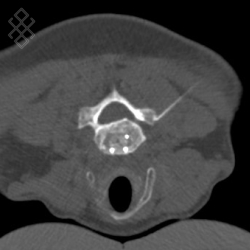

La durée de l'examen est d'environ 20 minutes. Le médecin radiologue fera un repérage de la région à infiltrer sous scanner. Ensuite, il effectuera une anesthésie locale pour introduire sous contrôle scanner une aiguille fine. Il contrôlera l'avancement de l'aiguille jusqu'au bon positionnement pour l'injection du corticoïde. Enfin, l'aiguille sera retirée et le soulagement pourra apparaître directement ou après deux jours.